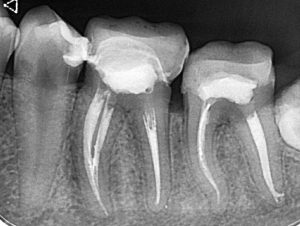

Пациентката беше изпратена в клиниката за консултация с „невъзможен за лечение“ зъб. Д-р Светломир Дамянов обича предизвикателствата и не му трябваше втора покана.

На снимките може ясно да се види ужасната и наистина невъзможна извивка.

Може да се види и прекрасно свършената работа с този зъб.